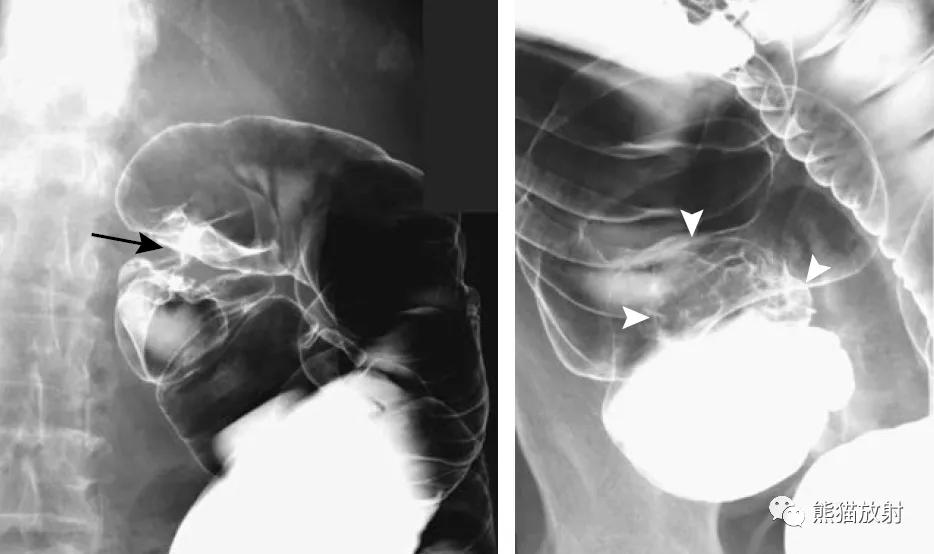

同一患者:结肠肝曲腺癌(黑箭)、升结肠腺瘤(白箭头)

升结肠癌(箭)和横结肠浸润性腺癌(箭头)。

钡灌肠筛查中发现了一个15mm的乙状结肠腺癌(箭头)。乙状结肠冗长。

结肠腺癌。肠壁环形增厚,苹果核征;可见溃疡形成(箭)。